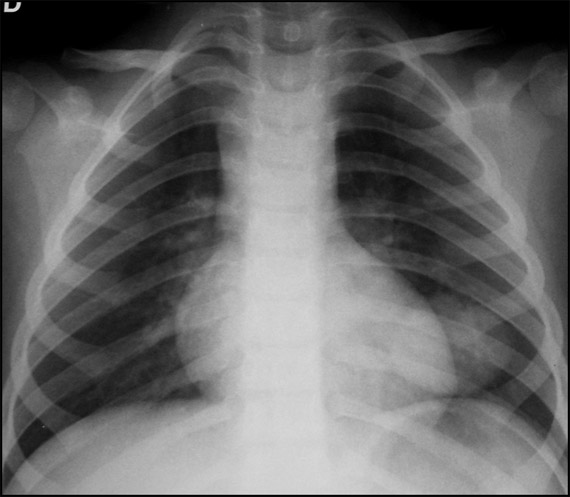

Neumonía redonda

La neumonía redonda es una manifestación atípica propia de niños menos de ocho años. Se observan aumentos de densidad focal de bordes bien definidos, de predominio en lóbulos inferiores.

Localice esta neumonía en la radiografía.